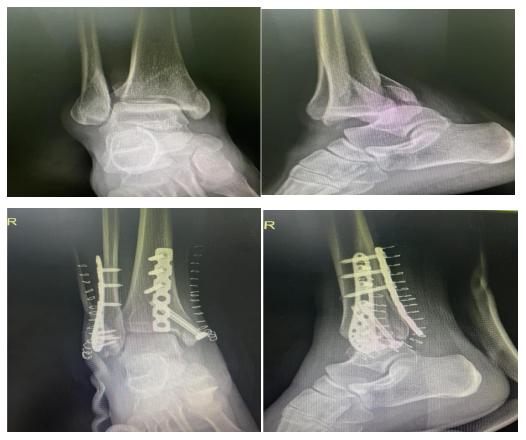

最近, 骨科贾鹏主任医师接诊了一位特殊的患者——小王在下楼梯时不慎崴脚,脚踝迅速肿胀、关节明显畸形。凭借此前了解的急救知识,她立即用硬纸板临时固定伤处,毛巾裹冰袋冷敷、患肢抬高20厘米,家人紧急送医后,拍片确诊为踝关节骨折。得益于前期科学处理,贾鹏主任及时为患者实施了手术,目前小王已康复出院。

崴脚后应尽快到骨科就诊,医生会通过体格检查+X光/CT/MRI,明确是韧带损伤、骨折还是关节不稳。像小王这类患者,若早期未正确固定、勉强行走,易导致骨折移位,若处理及时,部分骨折可避免手术创伤。